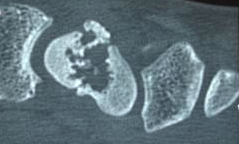

Bestehen weiter Zweifel, kann auch eine Computertomographie angefertigt werden.

Eine Computertomographie erlaubt eine überlagerungsfreie Darstellung des Kahnbeines und damit zu jedem Zeitpunkt eine sichere Beurteilung, sofern sie in Längsrichtung des Kahnbeines durchgeführt wird. Alternativ kann auch eine Magnetresonanztomographie angefertigt werden, hierüber entscheidet der Arzt.

Zur genauen Beurteilung der Bruchstücke und Planung der Operation kann ergänzend eine Computertomographie in Längsrichtung des Kahnbeins durchgeführt werden.